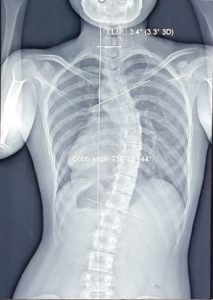

Sáng 16.6, bác sĩ Calvin Q Trịnh, Trưởng trung tâm hiệu chỉnh cơ xương khớp, Bệnh viện 1A cho biết, qua thăm khám cho thấy bệnh nhân bị vẹo cột sống ngực thắt lưng nặng với góc cobb (góc tạo ra giữa hai đường thẳng từ 2 đốt sống bị vẹo nặng nhất) 44 độ, mất độ ưỡn sinh lý cột sống cổ. Giảm độ ưỡn sinh lý cột sống L1-S1."Điều nguy hại là các đốt sống ngực đã biến dạng. Việc điều trị bảo tồn không thể trả lại hình dạng ban đầu", bác sĩ Calvin cho hay.Sau 12 buổi tập hiệu chỉnh cơ xương khớp, tình trạng đau mỏi lưng được cải thiện. Bệnh nhân có thể leo cầu thang được nhiều và không còn cảm thấy khó thở nhiều như trước đây. Hai vai bằng nhau và giảm lệch vẹo. Bệnh nhân được hướng dẫn thêm bài tập về nhà để tập luyện duy trì.cot-song-1 Hình chụp X-quang tình trạng cong vẹo cột sống của bệnh nhân. Ảnh: BSCCTương tự, bệnh nhân L.Đ, 18 tuổi, học sinh lớp 12. Hồi năm 13 tuổi, bệnh nhân đi khám và phát hiện vẹo cột sống tại một bệnh viện ở TP.HCM, được điều trị cho mang áo nẹp nhưng không xử trí thêm, sau nhiều năm vẹo cột sống ngày càng tiến triển, bệnh nhân vẫn chỉ mang áo nẹp liên tục.Đến 6.2023, bệnh nhân Đ. ngồi học nhiều nên xuất hiện nhiều triệu chứng đau mỏi cơ vùng cổ vai gáy và khó khăn trong sinh hoạt. Khi bệnh nhân đến Trung tâm hiệu chỉnh cơ xương khớp, Bệnh viện 1A khám, cho thấy vai trái lệch cao gần 5 cm so với vai phải, lồng ngực biến dạng, cột sống cong chữ S, nặng nhất ở đoạn ngực. Lệch vẹo khung chậu. Trên phim X-quang vẹo cột sống đoạn ngực chữ S rất nặng với góc Cobb là 53 độ , T6-T12 là 60 độ.